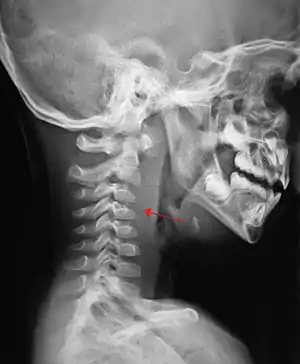

| A lateral cervical spine x-ray demonstrating prevertebral soft tissue swelling (marked by the arrow) as seen in a person with a retropharyngeal abscess | |

X-ray of the neck often (80% of the time) shows swelling of the retropharyngeal space in affected individuals. If the retropharyngeal space is more than half of the size of the C2 vertebra, it may indicate retropharyngeal abscess.[5]